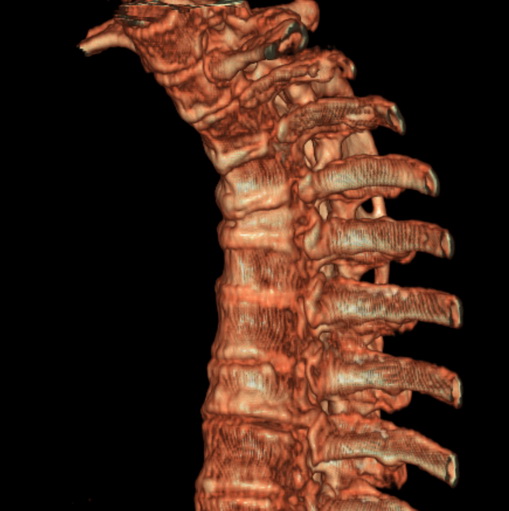

标题: CT25377:脊柱有无压缩骨折?

女、73、胸痛、胸闷3个月,无明显外伤病史,x线疑t4、t7陈旧压缩骨折,ct未经明显骨折,请问结论如何报?

老年女性病人,骨质稀疏,有些驼背,t4明显变扁,t7略变扁,椎体边缘无中断,骨小梁排列正常,无嵌插所致致密线。结合无明显外伤史,考虑老年骨质稀疏,慢性压缩改变,正如老年人骨质稀疏椎体呈双凹改变一样。我考虑报:老年骨质稀疏,t4、t7楔形变,脊柱曲度改变(驼背).敬请大家指教。

1)多个胸椎陈旧性压缩性骨折。2)胸椎普遍性骨质疏松。3)胸椎退行性改变。